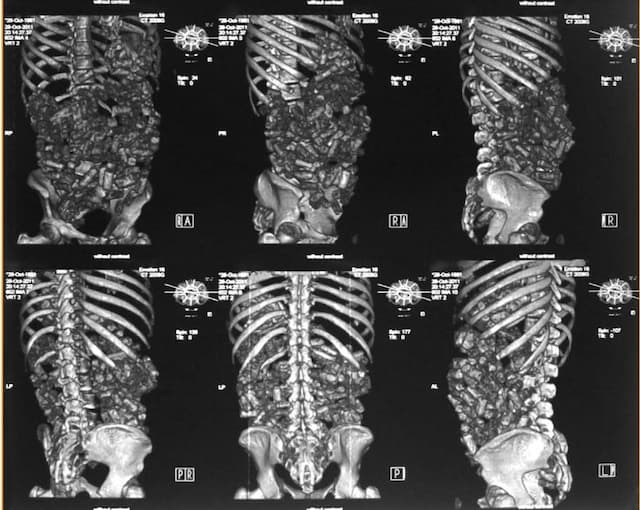

2. Computed Tomography (CT Scan)

CT scanning is a more sensitive and specific imaging technique than plain radiography, especially when complications such as packet rupture, perforation, or obstruction are suspected. Recent systematic reviews indicate that abdominopelvic CT without contrast is the preferred diagnostic modality for body packers, offering the highest sensitivity in detecting drug packets. Conservative management, including whole bowel irrigation, remains the first-line treatment, but early surgical intervention is necessary in cases of packet rupture or obstruction (Hassanian‐Moghaddam et al., 2019)

Key Features: Detects drug packets with greater clarity, even those missed by X-rays.

Advantages: Higher sensitivity, excellent for detecting leakage of drug contents, gastrointestinal obstruction, and perforation.

Limitations: Higher radiation exposure than X-ray, higher cost, and limited availability in some settings.